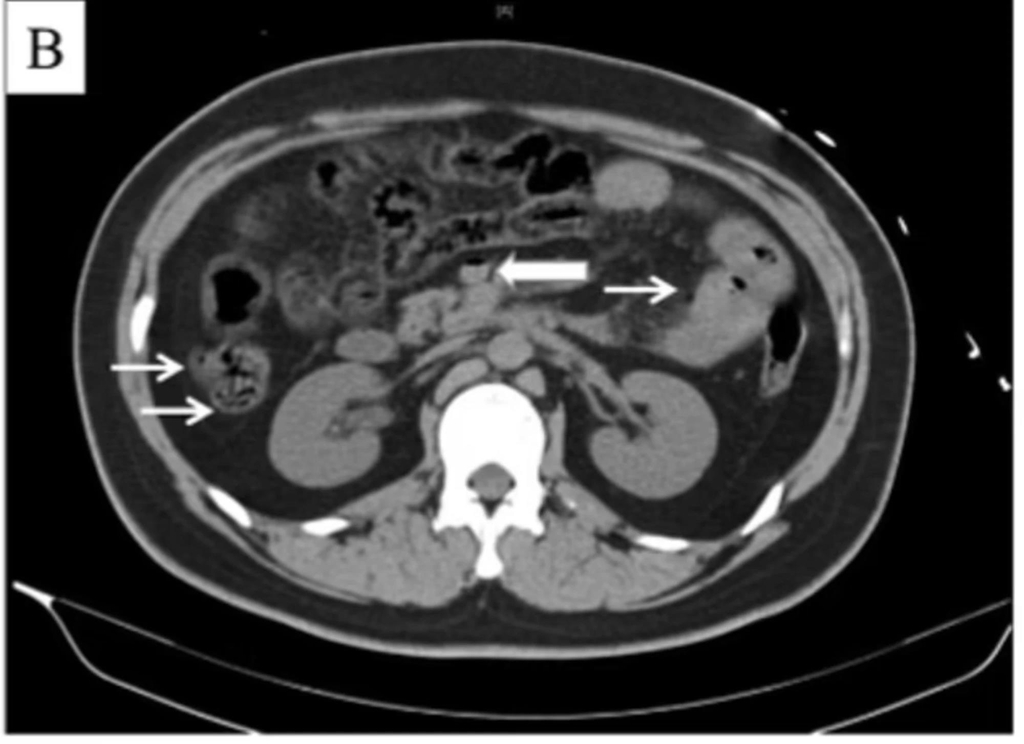

또 CT(컴퓨터단층촬영) 검사 결과 그의 장기와 간문맥(장과 간 사이의 혈관)에 평소와 달리 가스가 차 있었고, 간에서는 산소 공급 부족으로 장기가 손상되는 '허혈' 증세도 나타났다.

의료진은 이런 증상이 간문맥에 차 있는 가스와 연관된 것으로 판단하고 즉시 이를 빼내기 위한 조치에 나섰다.

의료진은 이번 사고를 두고 해당 남성이 급하게 콜라를 마신 뒤 장기에 가스가 축적됐고, 압력이 증가해 가스가 간의 주요 혈관인 간문맥으로 새어 들어간 것으로 보고 있다.

이는 또 간 손상을 유발해 사망으로 이어졌다고 판단한다.